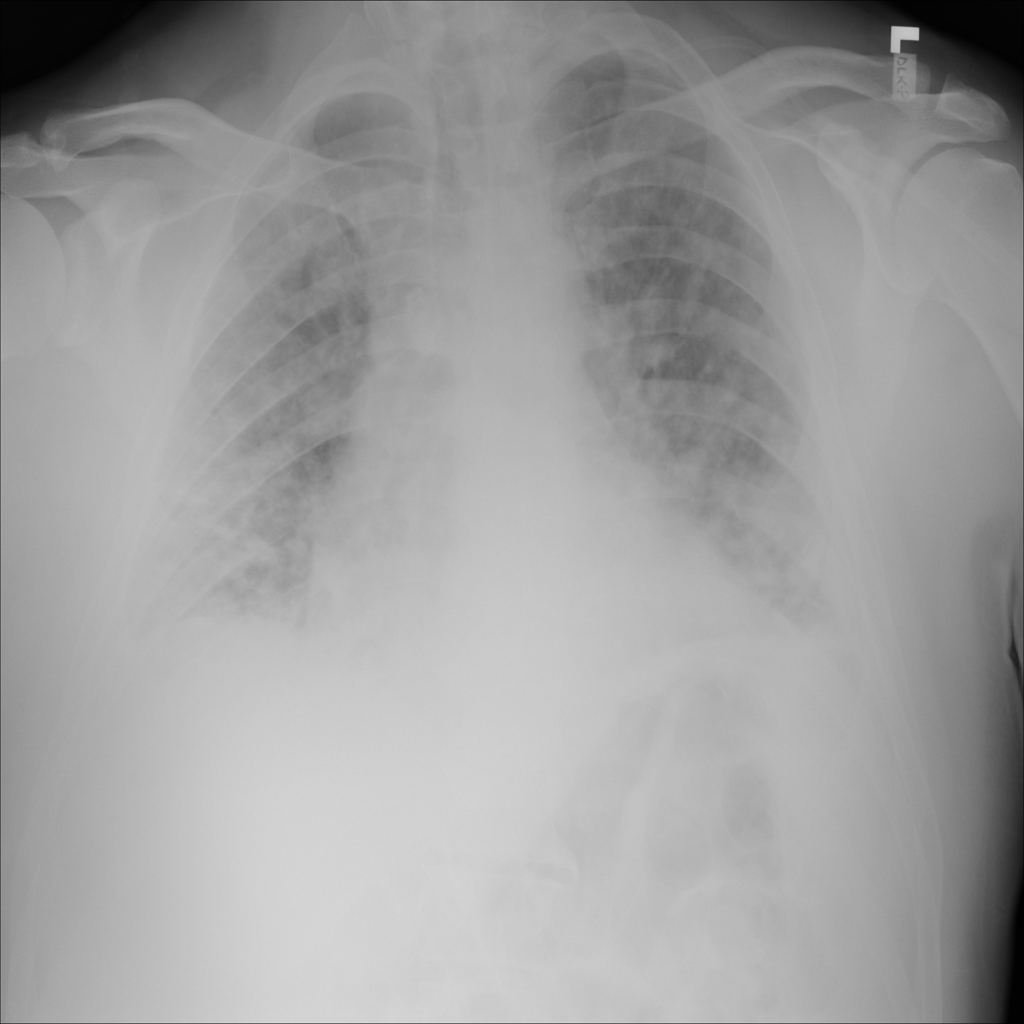

PAT-E828 · IMG-004Edema

PAT-E828 · IMG-004

AP